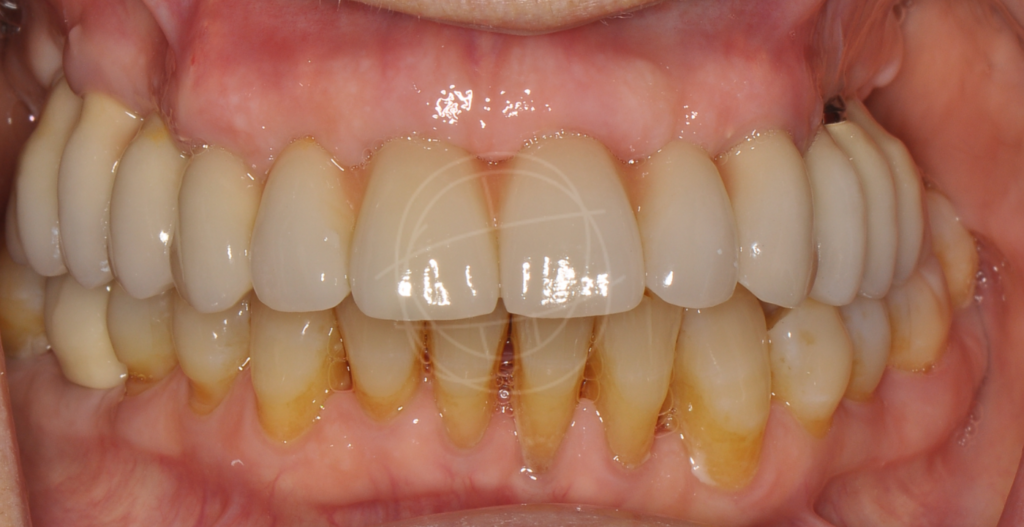

Ένα οδοντικό εμφύτευμα είναι μια «τεχνητή ρίζα» από βιοσυμβατό τιτάνιο, που τοποθετείται χειρουργικά στο οστό της γνάθου. Πάνω του στηρίζεται μια στεφάνη (το «τεχνητό δόντι»), η οποία μοιάζει και λειτουργεί όπως ένα φυσικό δόντι. Γι’ αυτό και συχνά τα εμφυτεύματα θα τα ακούσετε ως «βιδωτά» ή «φυτευτά» δόντια.

Η προσέγγιση που ακολουθούμε βασίζεται σε επιστημονικά πρωτόκολλα και εξατομικευμένο σχεδιασμό, ώστε κάθε ασθενής να έχει ένα φυσικό και μακροχρόνια επιτυχημένο αποτέλεσμα.

Φυσική εμφάνιση και αίσθηση

Μοιάζουν απόλυτα με φυσικά δόντια σε εμφάνιση και λειτουργία — συνήθως κανείς δεν καταλαβαίνει τη διαφορά.

Καλύτερη μάσηση

Η δύναμη μάσησης επανέρχεται σε φυσιολογικά επίπεδα, χωρίς περιορισμούς στις τροφές.